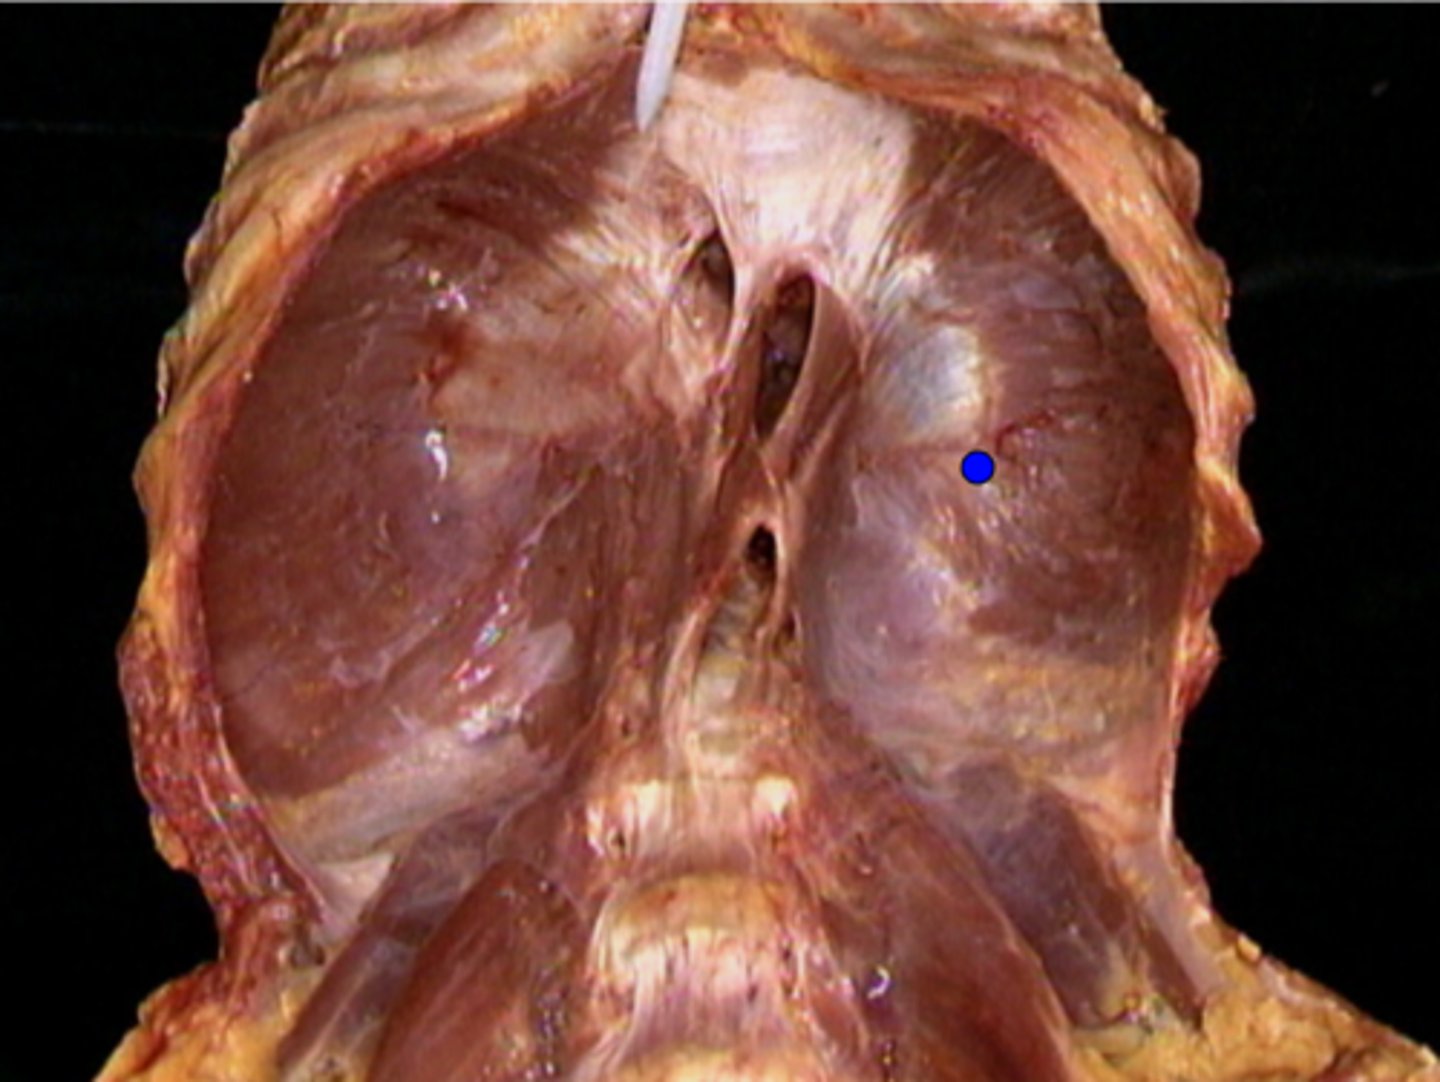

Diaphragm

Superior lobe of right lung

Middle lobe of right lung

Inferior lobe of right lung

Superior lobe of left lung

Inferior lobe of left lung

Lingula

Apex

Base/Diaphragmatic Surface

Costal Surface

Mediastinal Surface

Anterior Margin

Posterior Margin

Visceral Plurae